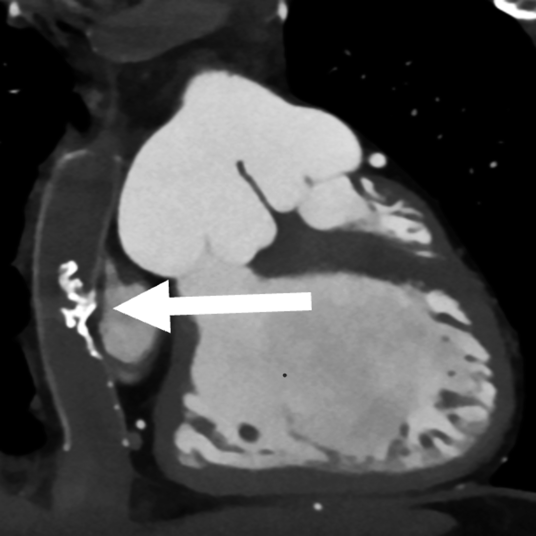

造影CT検査

導管内に粗大な石灰化あり,内腔の狭小化を認めた(Fig. 2).

Fig. 2 Preoperative computed tomography showing papillary calcification in the conduit in patient 1